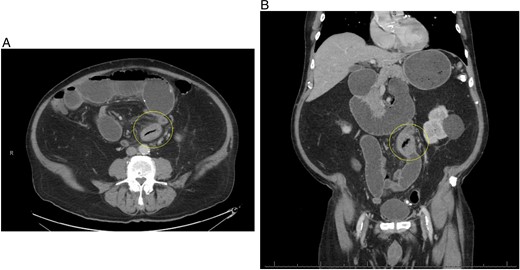

The postoperative course was complicated by ileus, which did not resolve until postoperative day 11. The patient was discharged in stable condition and returned to the hospital 3 days after with oral administration intolerance. At this time, abdominal examination revealed significant abdominal distention. Incisions were healed and non-tender. A repeat abdominal CT scan showed dilated fluid-filled loops of the small bowel consistent with high-grade small bowel obstruction and focal intussusception of a loop of the small bowel distal to the small bowel anastomosis with associated wall thickening (Fig. 2). Over the next two weeks, the patient had a tumbling small bowel obstruction. His abdominal symptoms improved and worsened cyclically. A small bowel follow through was obtained and showed contrast within the colon in 45 min, signifying partial and incomplete obstruction. Esophagoduodenoscopy revealed two duodenal diverticulum. On hospital Day 13 during the patient’s second admission, he developed severe abdominal pain and was taken back to the operating room for a second diagnostic laparoscopy, which revealed an inflamed small bowel distal to the previous fully healed small bowel anastomosis. After manual palpation, we observed a hard mobile mass within the small bowel. An enterotomy was performed, and a 5 × 4 cm calcified stone appeared to cause pressure necrosis of the small bowel mucosa. The stone was round and without any facets (Fig. 3). Primary repair of the small bowel was then performed. The entire small bowel run from the ligament of Treitz to the cecum, and no additional stones or pathology was palpated except for a small 1.5 cm meckel diverticulum ~2 feet proximal to the ileocecal junction. The patient recovered well after surgery. Abdominal bloating and pain resolved, and the patient began tolerating the diet by postoperative day 2. The patient was seen as an outpatient in the clinic and has been doing well for 3 months after surgery.

(A) Repeat CT scan (transverse view) on readmission revealing the same primary enterolith with the core pit that mimics intussusception. (B) Repeat CT scan (coronal view) on readmission revealing the same primary enterolith with the core pit that mimics intussusception.